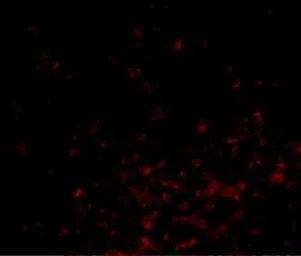

IHC-P analysis of human lymph node tissue using GTX31737 Bag1 antibody.

Working concentration : 20 μg/ml